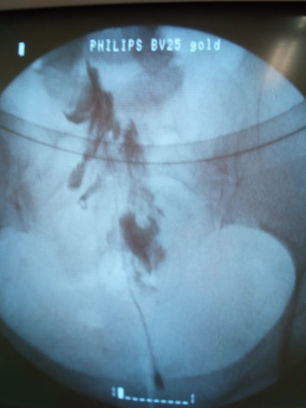

Μία από αυτές είναι η απονεύρωση των αισθητικών κλάδων της άρθρωσης του γόνατος (genicular nerves radiofrequency ablation) με ραδιοσυχνότητες, υπό ακτινοσκοπική ή υπερηχογραφική καθοδήγηση. Τα νεύρα αυτά είναι καθαρά αισθητικοί κλάδοι και η καταστροφή τους μέσω ραδιοκαύσης προκαλεί αναλγησία η οποία διαρκεί από 3 μήνες έως και 1 έτος σε ορισμένους ασθενείς.

Η όλη διαδικασία δεν διαρκεί περισσότερο από 30 λεπτά, γίνεται υπό άσηπτες συνθήκες χειρουργείου και υπό ακτινοσκοπική ή υπερηχογραφική καθοδήγηση και ο ασθενής μετά από 1 ώρα μπορεί να επιστρέψει στο σπίτι.